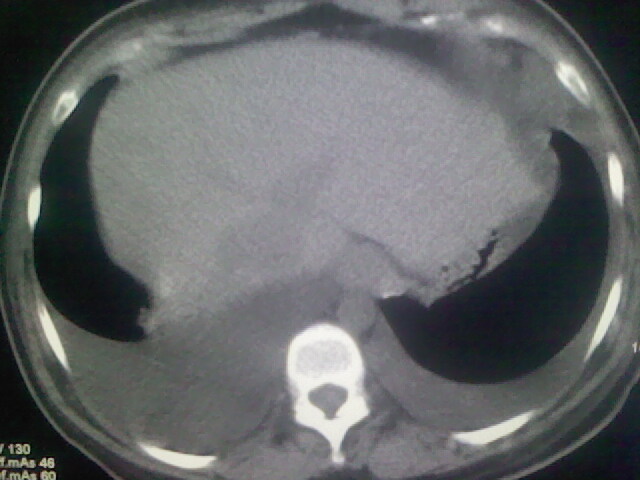

女,24,剖腹产后,突觉胸痛,干咳,不能平卧

胸水 感染 心影增大 肺水肿?

双肺“肺泡性肺水肿” “胸腔积液”!

双侧胸腔积液,肺泡性肺水肿。后纵隔好像有占位。

肝脾大,双侧胸腔积液,双肺水肿,肺动脉[包括远端小动脉],左右心房,左心室增宽,右心室主动脉无明显改变,符合左心功能不全征;;建议除外二尖瓣关闭不全,扩张性心肌病